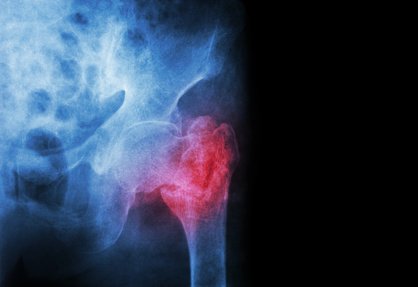

Vuoi navigare al meglio dal tuo smartphone? Vai alla pagina ottimizzata AMP (Accelerated Mobile Pages)Il collo del femore unisce la testa sferica alla diafisi femorale, sopportando così il carico che si trasmette al terreno.Verso la base del collo si inserisce la capsula articolare, che unisce il femore al bacino mantenendo fissa la testa nell’acetabolo.

La capsula articolare è molto robusta perché deve sopportare i limiti dell’estensione articolare, aiutata da legamenti anteriori e posteriori e contiene la quasi totalità dei vasi che nutrono la testa del femore.

Le fratture del femore si vericano molto spesso nell’età anziana e tra le donne, o per evento traumatico nei giovani (soprattutto per incidenti stradali).

Le fratture del collo del femore si dividono in:

Un tipo di trattamento chirurgico è l’osteosintesi, riduzione della frattura attraverso viti di acciaio o di titanio. Possibili complicanze di questo tipo di intervento sono la necrosi della testa del femore e la pseudoartrosi che sono riconducibili all’interruzione dell’apporto vascolare alla testa del femore in seguito al trauma.